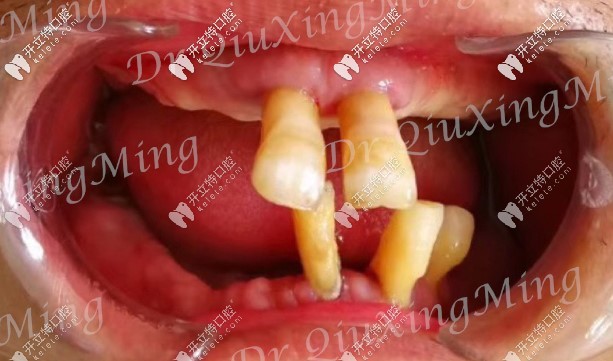

這是大爺做完種植牙的口腔情況↓

上下各4顆種植體,還裝了臨時(shí)牙冠,種植牙手術(shù)當(dāng)天就完成了。這速度,嘖嘖嘖.....